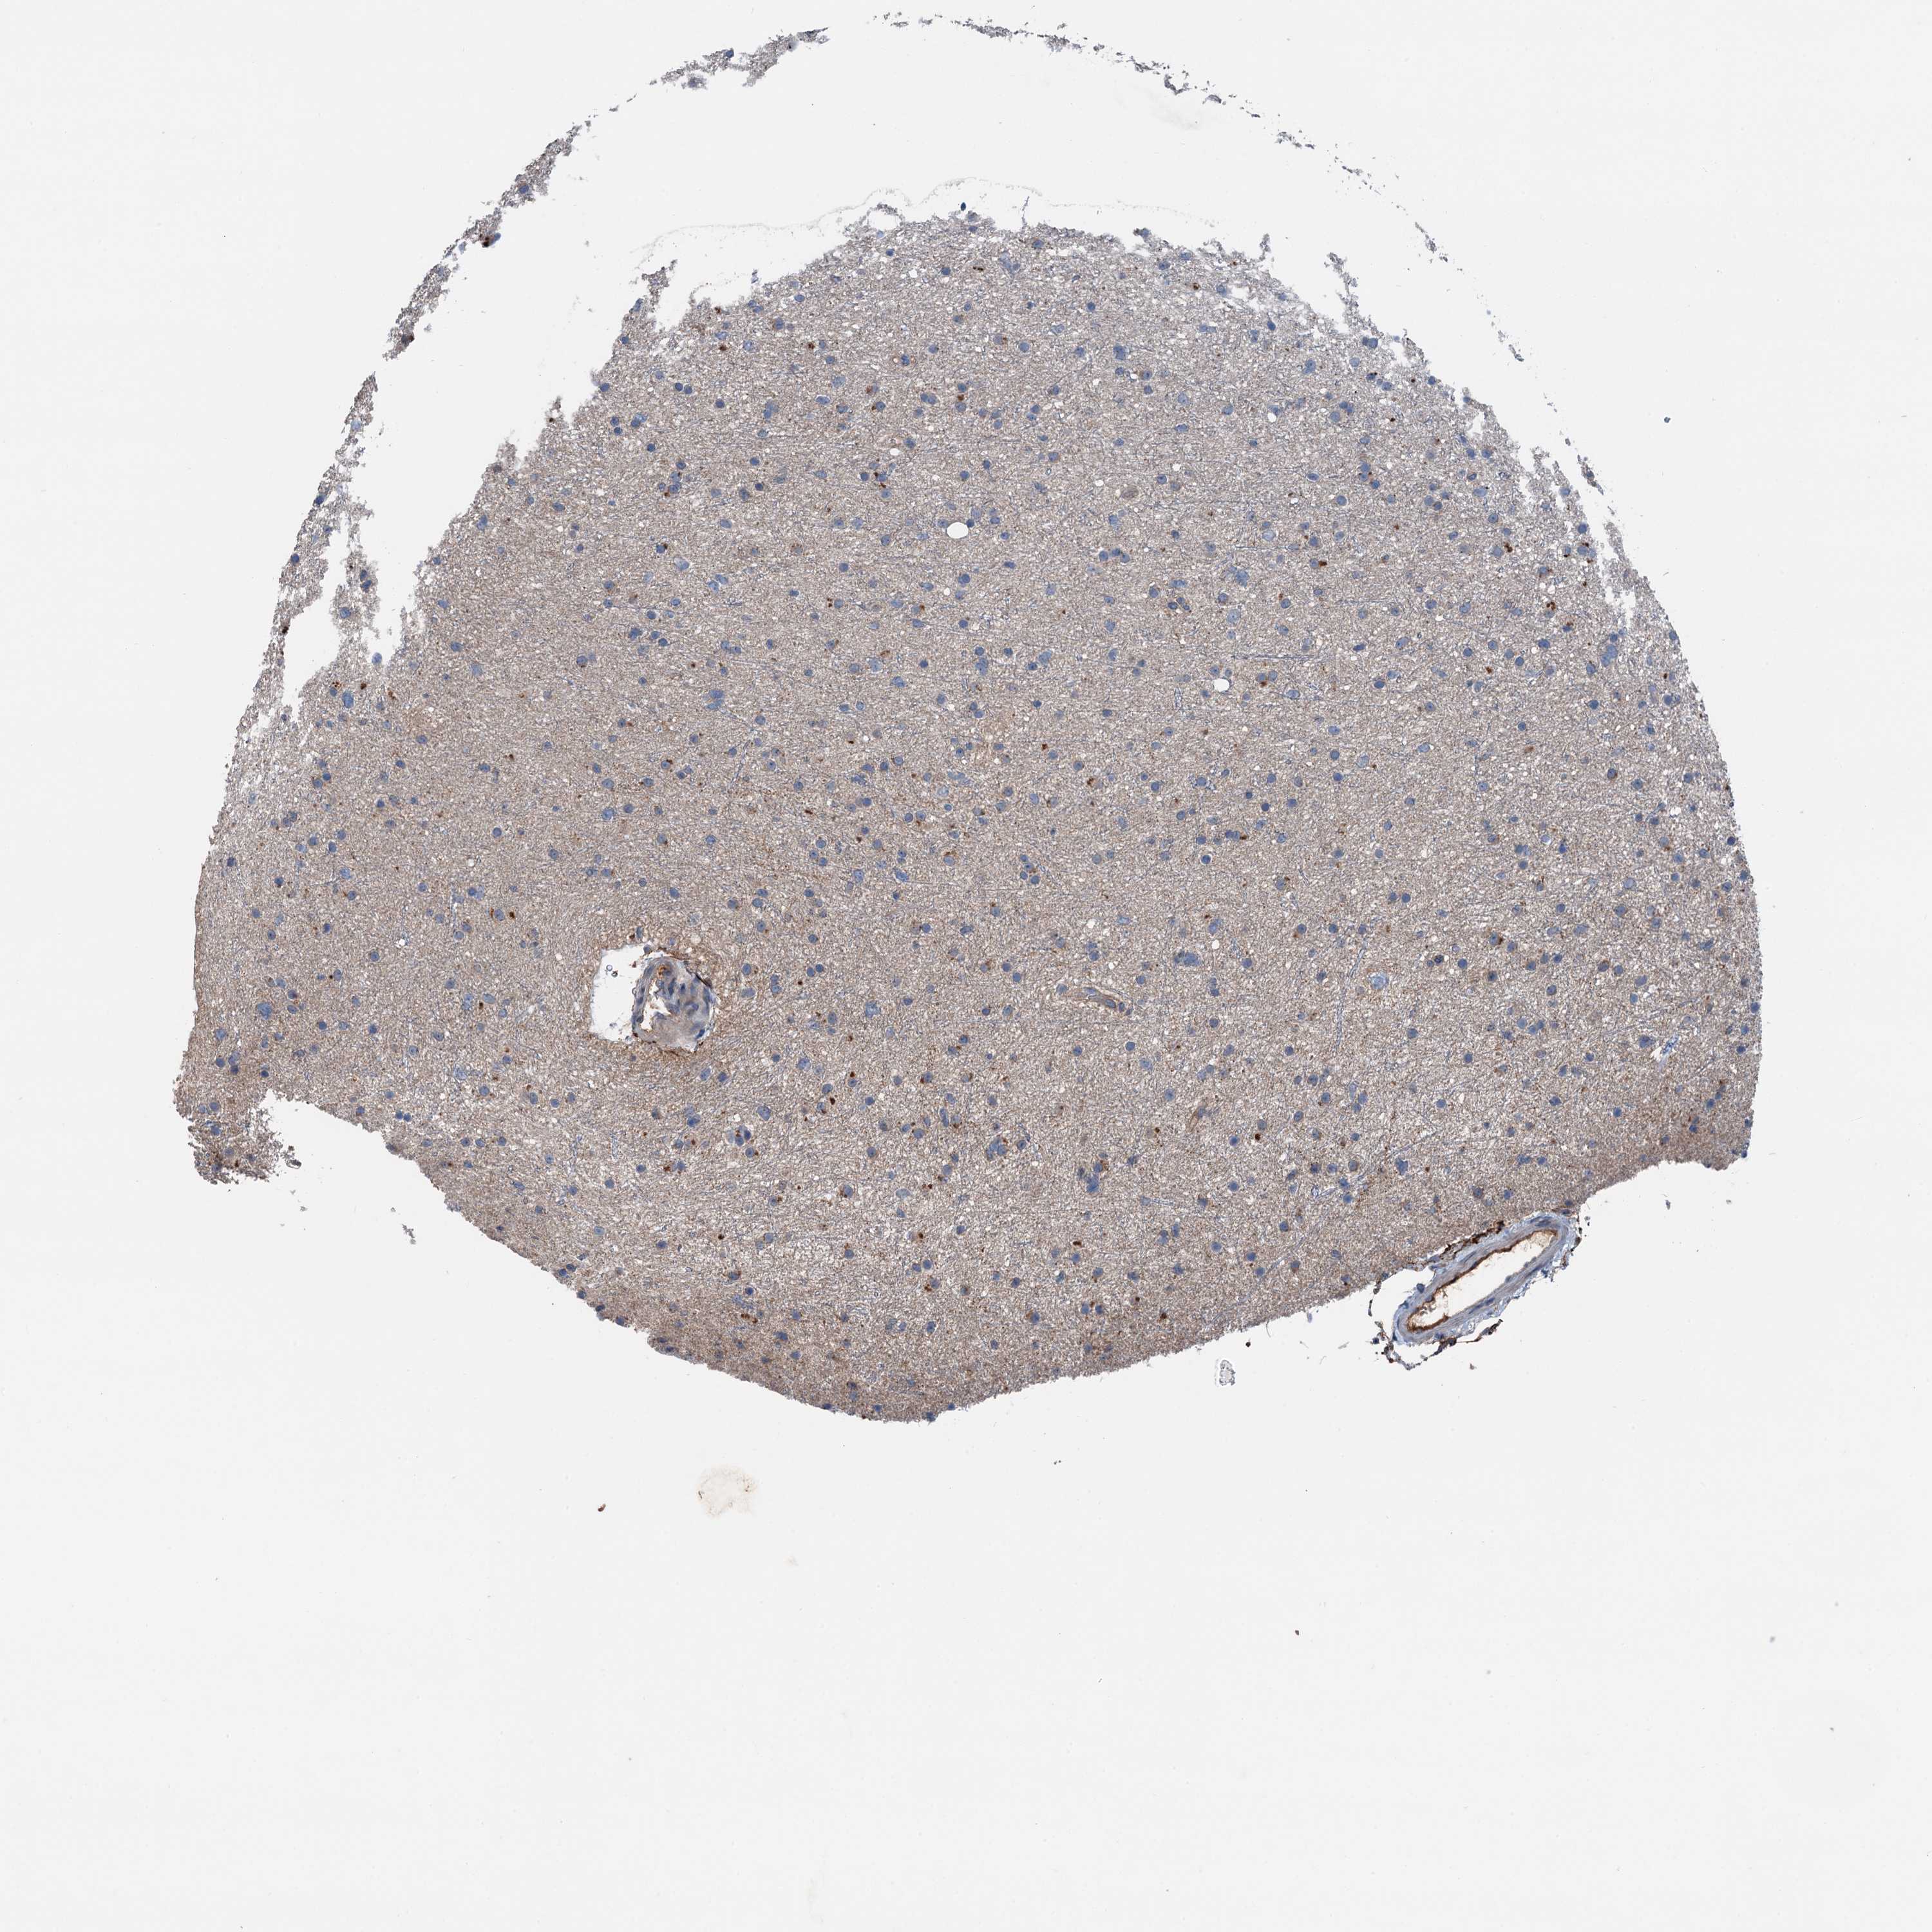

GLIOMA - Protein expressioni

A mouse-over function shows sample information and annotation data. Click on an image to view it in a full screen mode. Samples can be filtered based on level of antibody staining by selecting one or several of the following categories: high, medium, low and not detected. The assay and annotation is described here.

Note that samples used for immunohistochemistry by the Human Protein Atlas do not correspond to samples in the TCGA dataset.

Antibody stainingi

Antibody staining in the annotated cell types in the current human tissue is reported as not detected, low, medium, or high, based on conventional immunohistochemistry profiling in selected tissues. This score is based on the combination of the staining intensity and fraction of stained cells.

Each image is clickable and will lead to virtual microscopy that enables deeper exploration of all samples and also displays staining intensity scores, fraction scores and subcellular localization as well as patient and tissue information for each sample.

Antibody HPA041015

Staining

High

Medium

Low

Not detected

Intensity

Strong

Moderate

Weak

Negative

Quantity

>75%

75%-25%

<25%

None

Location

Nuclear

Cytoplasmic/membranous

Cytoplasmic/membranous,nuclear

Glioma, malignant, High grade

Glioma, malignant, Low grade